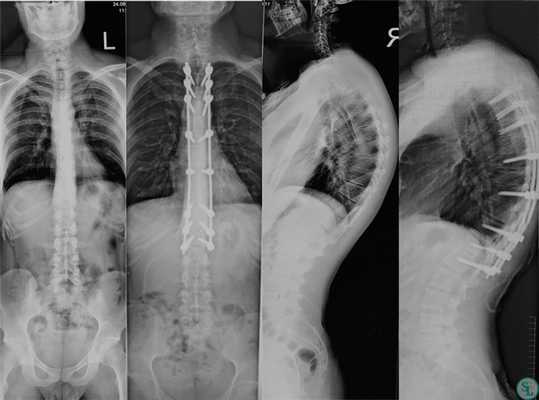

Пациент 27 лет из Московской области, поступил с жалобами на боли в грудном отделе позвоночника, деформацию грудного отдела. Данные жалобы беспокоили около 1 года.

На рентгенограммах позвоночника- грудо-поясничный кифосколиоз на фоне Болезни Шейермана-Мау, угол кифоза 76° по Cobb.

Изучив предыдущие рентгенограммы, мы выяснили, что деформация неуклонно прогрессирует. Учитывая клинико-рентгенологическую картину и неэффективность консервативных методов лечения, нами было принято решение о необходимости оперативного вмешательства.

Была выполнено оперативное лечение - Дорсальная коррекция фиксация позвоночника транспедикулярной системой. Корригирующая остеотомия на вершине деформации. Костная пластика.

Время операции 3 часа. На следующий день после операции пациент был активизирован, начал сидеть и вставать.

на 4 сутки с моментоперации

На контрольных рентгенограммах отмечена коррекция грудного кифоза до физиологической нормы, угол кифоза после операции составил 61° по Cobb.

рентген позвоночника до и после оперативного лечения

Пациент в удовлетворительном состоянии выписан на 4 сутки с момента операции.